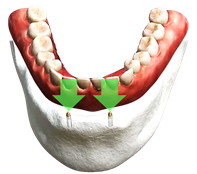

그런데 아래쪽 잇몸에 임플란트 2개를 심고 틀니를 연결하여 고정하는 임플란트 틀니의 경우 잘 움직이지 않아 음식을 부수어 먹는 수준 정도는 되기 대문에 식생활을 조금이나 편하게 해 준다.